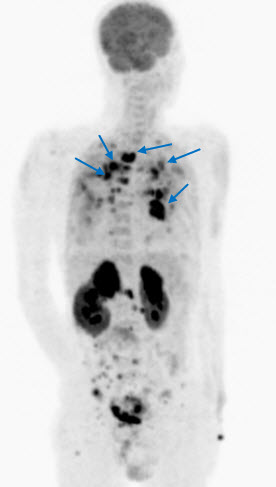

Một trong những điểm mạnh của PET/CT là có thể phát hiện được các tổn thương trong cơ thể chỉ qua một lần chụp. Tổn thương hạch là triệu chứng phổ biến nhất của u lympho ác tính không Hodgkin. Ngoài hạch, PET/CT còn có thể phát hiện được các tổn thương ở xương, phổi, não, gan, lách...

Mai Trọng Khoa và cộng sự đã tiến hành chụp 18FDG-PET/CT cho các bệnh nhân bị u lympho ác tính và nhận thấy các tế bào ác tính tại u nguyên phát và các tổ chức di căn hấp thu mạnh 18FDG và có sự chênh lệch rõ rệt hoạt độ phóng xạ của dược chất phóng xạ này so với các tổ chức xung quanh. Vì vậy 18FDG-PET/CT rất có giá trị trong chẩn đoán u nguyên phát và phát hiện các di căn của u lympho ác tính không Hodgkin với độ chính xác cao. Có thể thấy rõ hơn những nhận định trên qua các hình ảnh PET/CT của một số bệnh nhân u lympho ácc tính không Hodgkin tại Trung tâm Y học hạt nhân và Ung bướu, bệnh viện Bạch Mai.

Hình 1. Bệnh nhân Vũ D.L., nam, 56 tuổi. Chẩn đoán: Non Hodgkin Lymphoma , GPB: WF7. Hình PET/CT toàn thân thấy tổn thương hạch ở nhiều vị trí: vùng cổ, trung thất, hố nách, ổ bụng, bẹn (các mũi tên) tăng hấp thu FDG.